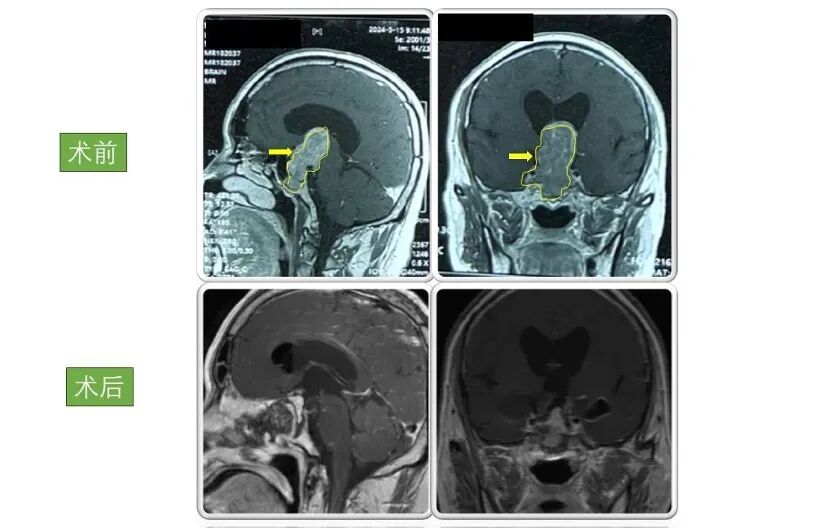

患者1:

男性,46岁 因“突发头痛伴恶心呕吐、双眼视物不清12小时”入院。入院检查显示巨大垂体腺瘤,大小为4.5×4×4cm。

术后患者双眼视力明显好转,病情稳定后出院,现恢复良好,定期复查。